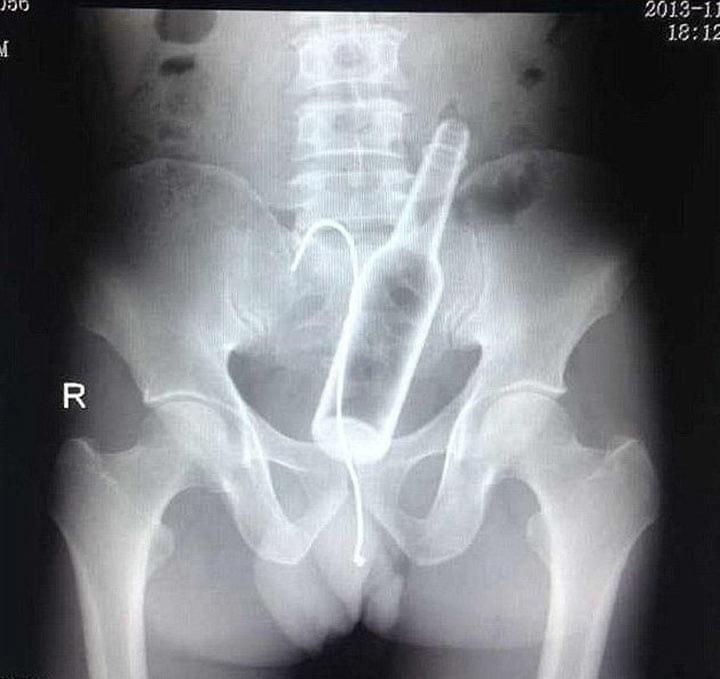

5. Несчастные случаи происходят Бутылка от дезодоранта в теле парня. Догадаетесь где именно?